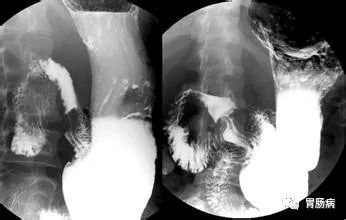

1、胃肠钡餐检查

是让患者口服造影剂硫酸钡,在X光透视及拍片时,利用钡剂在胃肠道留下的影像来判断胃和十二指肠内部的病变情况。

但是因为钡餐检查是很粗犷的检查,也不能活检组织,所以目前接受这种检查的患者越来越稀少。

这个项目更多的被用于诊断胃下垂、胃动力异常、贲门失弛缓等方面。